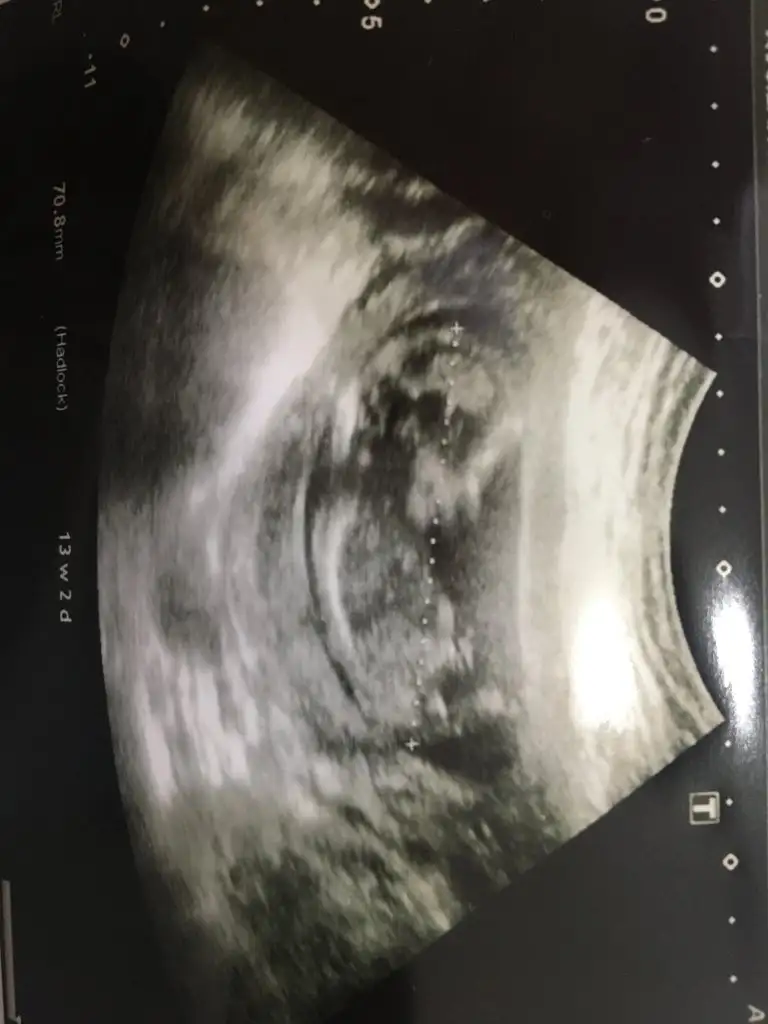

dr soylemeden siz gorun genital nub teorisi ( bebegin cinsiyeti)

Arkadaşlar lutfen tahmin eder misiniz